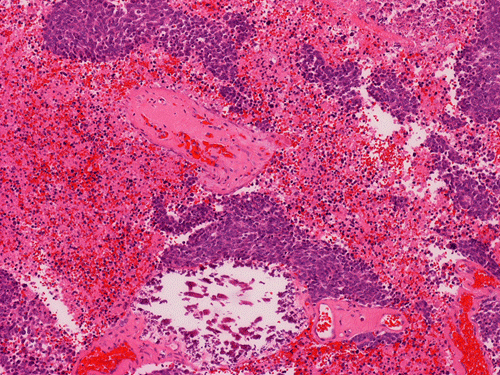

On permanent sections, there is extensive necrosis (Panel G) and there are numerous small islands of pyknotic or apototic nuclei (Panel H). In non-necrotic areas, the nuclei are large and pleomorphic. There are numerous mitotic figures (Panel I). Nuclear wrapping (Arrow in Panel J) is readily seen. The tumor is focally positive for synaptophysin, neurofilament proteins, glial fibrillary acidic protein, and diffusely positive for antibody BAF47.

Large cell (anaplastic) medulloblastoma is characterized by large, vesicular nuclei that are 5 times or more the size of a red blood cell. Marked variation in nuclear size and contour, and multinucleated, bizarre giant cells are other features. In particular, nuclear hugging or nuclear wrapping which refers one nucleus being surrounded by other nuclei as illustrated in this cases is a classic features of large cell medulloblastoma. In contrast to the classic type of medulloblastoma, the nucleoli are prominent, necrosis is prominent and extensive, extensive apoptotic or pyknotic cells are common. Large cell medulloblastomas have numerous mitotic figures that far exceed what would be expected in a classic medulloblastoma. Attempts has been made for a grading system of anaplstic changes in medulloblastoma 1 but the value of this system still has to stand the test of time 2, 3.